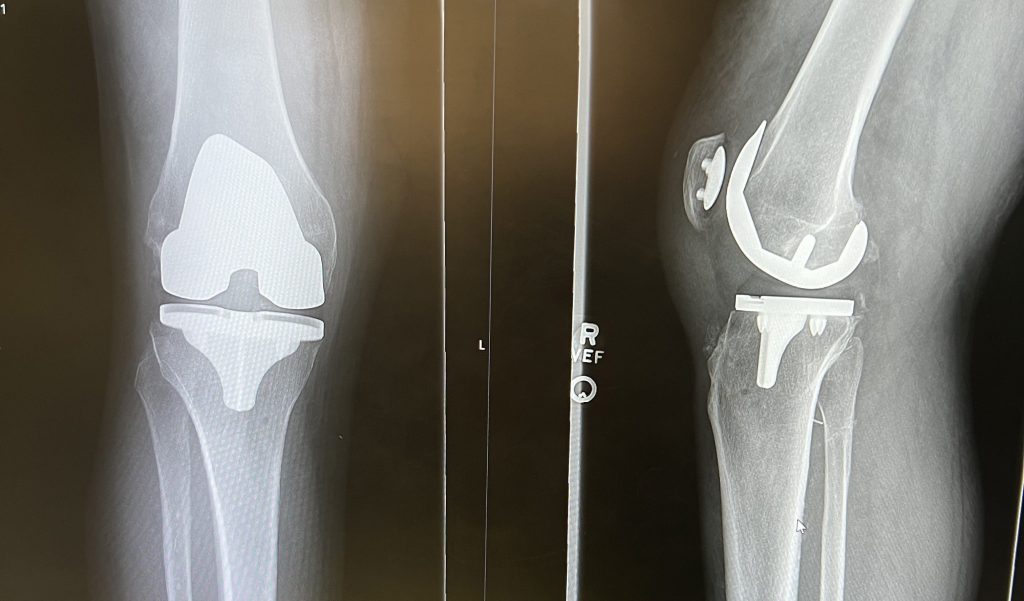

I had been having knee pain for years after my professional wrestling career and needed treatment for my knee pain. I was referred to Dr. Jonathan Vigdorchik and I couldn’t be happier with the results and care I received at HSS and with Dr. Vigdorchik and his staff. I highly recommend him for any treatments or surgeries you need to get your quality of life back after surgery. He’s number one in my book!

Jonathan M. Vigdorchik, MD

Hip and Knee Replacement and Hip Preservation Surgeon

Knee Replacement